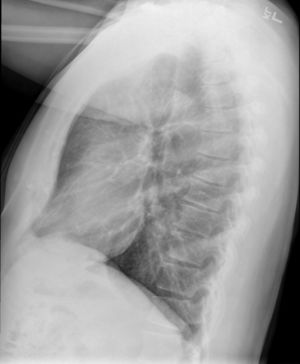

Medical imaging

Early in the disease chest radiography is typically normal but may show hyperinflation.[6] As the disease progresses a reticular pattern with thickening of airway walls may be present.[4][6] HRCT can also show air trapping when the person being scanned breathes out completely; it can also show thickening in the airway and haziness in the lungs.[11] A common finding on HRCT is patchy areas of decreased lung density, signifying reduced vascular caliber and air trapping.[6] This pattern is often described as a "mosaic pattern", and may indicate obliterative bronchiolitis.[6]